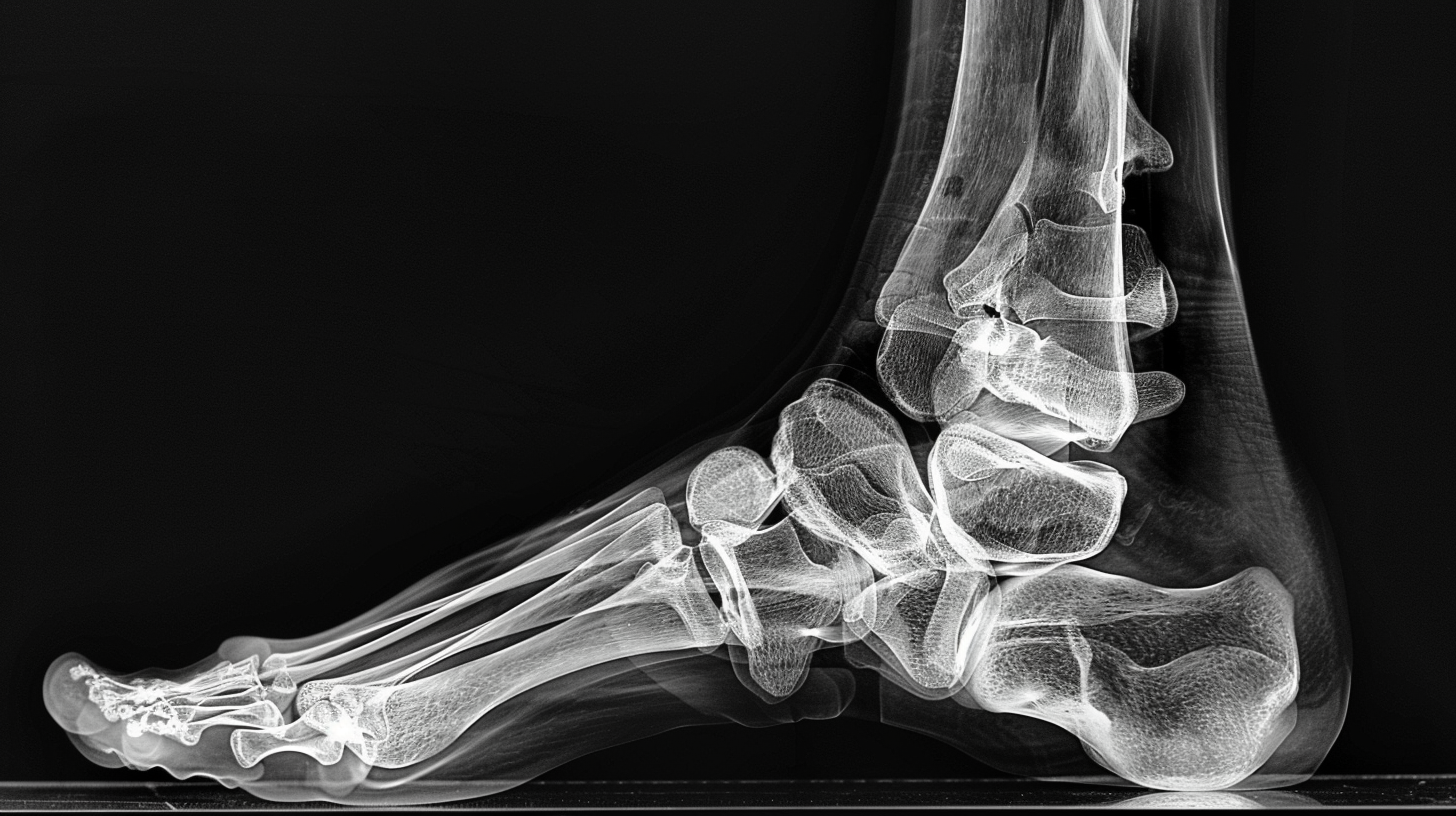

Рентген стопы

Рентгенография стопы назначается при диагностике плоскостопия, артрита, артроза, подагры, после травм, вывихов и переломов, до и после проведения операций на голеностопе, а также чтобы выяснить причину боли во время ходьбы. Позволяет оценить особенности строения, выявить врожденные патологии, деформации стопы и дегенеративные процессы. Рентген обеспечивает детальное изображение костей и суставов исследуемой части тела.